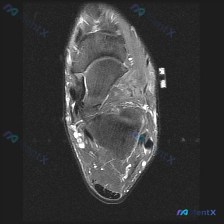

最近看到这个踝关节MRI病例,原始观察提示有软组织积液,整理一下完整的影像信息和分析思路给大家讨论。 一、基本影像信息 这是一张踝关节跟骨区域的矢状位T2加权脂肪抑制(或STIR)序列MRI,液体/水肿呈现高信号,脂肪信号被抑制,方便观察软组织病灶。 二、影像可见的核心异常 1. 骨骼结构:跟骨后上...

拿到这张踝关节MRI T2轴位片,问题问软组织液有什么表现,整理一下病例信息和分析思路给大家参考: 基本影像信息 这是踝关节MRI T2序列轴位图像,核心发现是: 1. 骨骼:距骨等主要骨性结构轮廓连续,无明显骨皮质中断,骨髓无大范围明显T2高信号水肿 2. 肌腱韧带:外侧腓骨长短肌腱走行区可见不规...